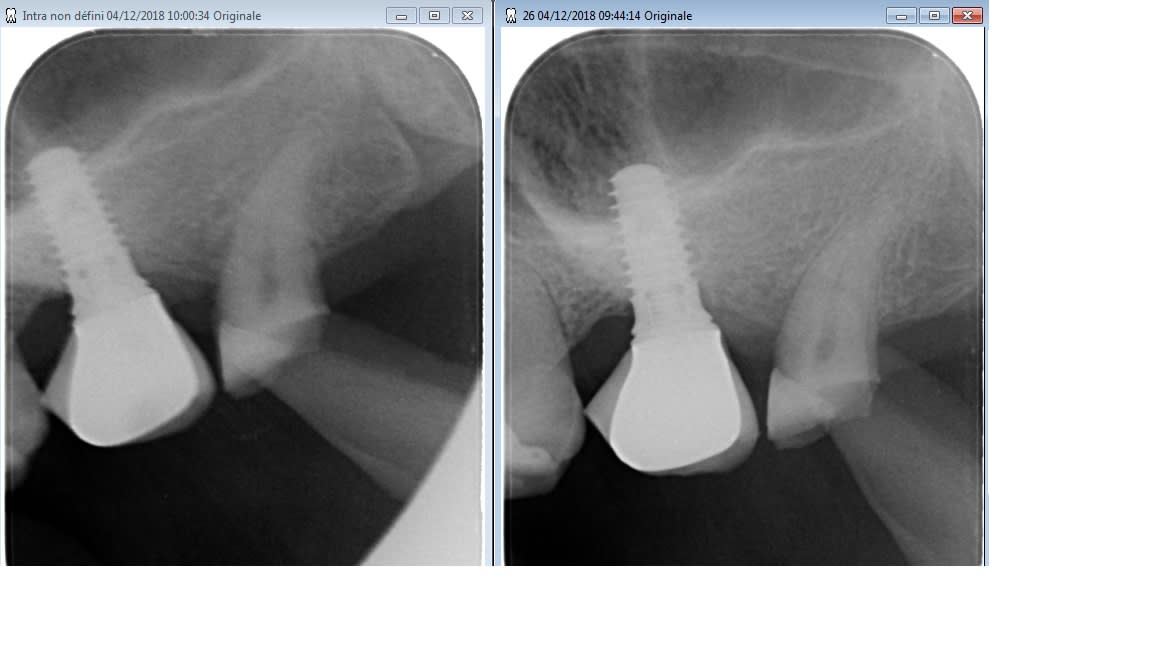

Bonjour à tous, implant posé en 2014, ccm scellé dessus à refaire car gros éclat de céramique.

Une idée du type d'implant.

maintenant vu la gueule de l'implant, amha c'est un octogone interne type "straumann"....

possible...mais comme j'ai un doute (au niveau de la forme du col)...